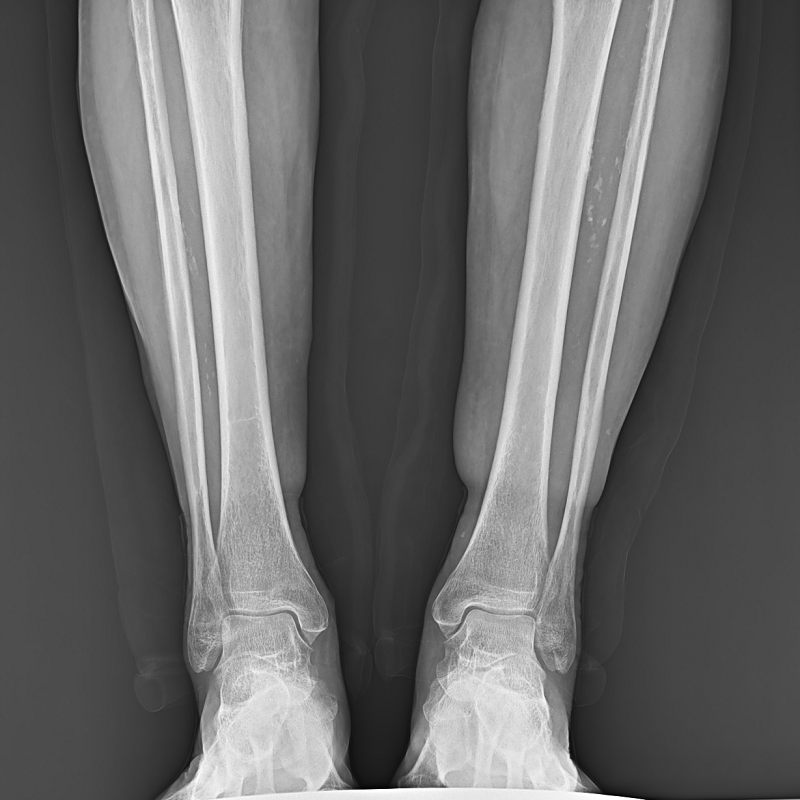

●呈現(xiàn)全下肢或全脊柱圖像

●在脊柱及下肢畸形矯正手術(shù)治療中,為術(shù)前方案制定和術(shù)后復(fù)查提供精準(zhǔn)測(cè)量

●有效解決傳統(tǒng)X光片不能一次成像問題,為患者提供更加優(yōu)質(zhì)的醫(yī)療服務(wù)

點(diǎn)片裝置可實(shí)現(xiàn)大范圍縱向移動(dòng),高效完成各部位、全身拼接等檢查需求